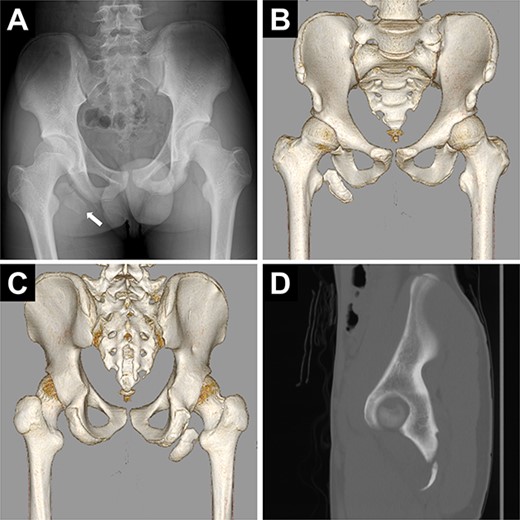

Pelvic images revealed the avulsion fracture of the right ischial tuberosity with severe displacement of the avulsed fragment (Fig. 1A–D). We performed ORIF 5 days after the injury. The patient was placed in the prone position under general anesthesia with the hip and knee joints in slight flexion (Fig. 2A). A 10-cm longitudinal skin incision was made 1 cm lateral to the ischial tuberosity and the subgluteal approach was performed (Fig. 2B). The avulsed fragment was displaced in the distal direction (Fig. 3A) and repositioned by posterior extension of the hip and flexion of the knee joint.

Preoperative images of the pelvis. (A) Pelvic radiograph showing the displaced avulsion fracture of the ischial tuberosity (white arrow). (B, C) Computed tomography scans show the displaced avulsed fragment. The avulsed fragment was displaced by 35 mm. (D) The size of the avulsed fragment was 55 × 17 mm.